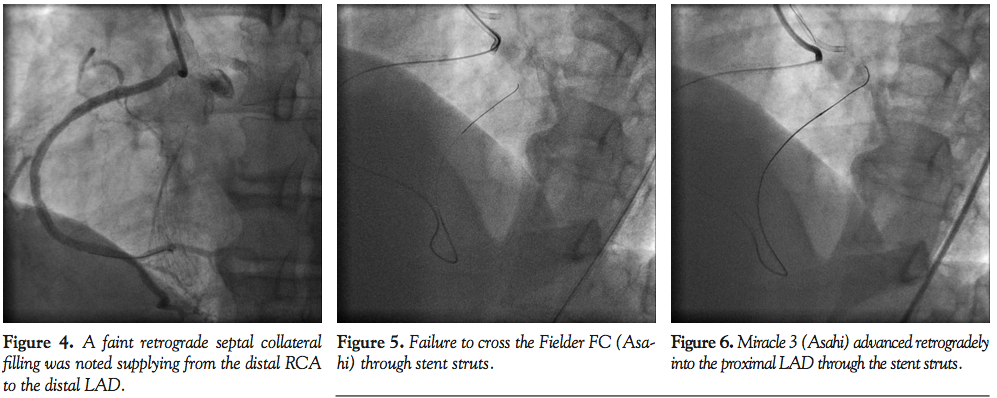

RunthroughNS Floppy (Terumo), Rinato (Asahi), and Balanced Middleweight Universal (Abbott Vascular), respectively. A 2.5 x 15 mm balloon was delivered to dilate along the LM and LAD. After intravascular ultrasound (IVUS) examination, a 3.0 x 33 mm Xience Prime stent (Abbott Vascular) was deployed from LM into LAD across the ramus and LCX. Ramus wire was removed (Figure 3). LCX wire was removed and re-crossed. The stent was postdilated with a 3.5 x 15 mm non-compliant balloon. Finally, kissing balloon inflation was performed with a 3.5 x 15 mm balloon and a 2.5 x 15 mm balloon inflated at 12 atm and 10 atm, respectively. A 6 Fr Judkins Right 4 guiding catheter was used to engage the anomalous RCA. A 3.5 x 23 mm Xience V stent (Abbott Vascular) was deployed at the mid RCA lesion and postdilated with a 4.0 non-compliant balloon. However, a faint retrograde septal collateral filling was noted going from distal RCA to distal LAD (Figure 4). What was thought to be the distal LAD was in fact a large diagonal branch. Effectively, we had deployed our stent across a LAD CTO from LM to diagonal. Therefore, the original LAD CTO became jailed under this stent. Multiple attempts were made to wire the totally occluded lesion antegradely, but were unsuccessful. Retrograde approach was attempted. The right femoral artery was accessed. A 6 Fr Amplatz left 1.0 guiding catheter (Medtronic) was introduced through the right femoral sheath and engaged into the RCA. The septal collateral was wired with Fielder FC (Asahi) supported by Corsair (Asahi) catheter. The Fielder FC was successfully advanced into the mid LAD but was unable to advance into the proximal LAD through the stent struts (Figure 5). It was then switched to Miracle 3 wire (Asahi) which successfully punctured through the jailed LAD stent strut and could reach the proximal LAD (Figure 6). The Corsair was tracked into the CTO (Figure 7). However, only the very tip of the Corsair could get through the stent strut and was stopped from advancing any further by the stent struts. Without enough support from the Corsair, we failed to externalize any of the retrograde guidewire despite sequentially changing to Fielder FC, Whisper (Abbott Vascular) and Rotawire (Boston Scientific). We decided at this stage to attempt a new method. The retrograde wire was withdrawn back into the Corsair and PT2 (Boston Scientific) was used as the antegrade wire to probe at the tip of the Corsair, which was situated just distal to the LAD stent strut. This antegrade wire probing technique was successful (Figures 8 and 9). The PT2 was manipulated into the Corsair. The retrograde system was removed and the PT2 was further advanced into the distal LAD (Figure 10). It was very difficult to track a balloon through the LAD stent strut into the mid LAD. A 1.25 mm balloon could cross the stent strut and was dilated up to 12 atm. But when we upsized the balloon to 1.5 mm, the balloon ruptured, causing extensive dissection with intramural hematoma down the mid